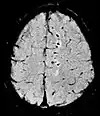

Susceptibility-weightedSWISpoiled gradient recalled echo (GRE), fully flow compensated, long echo time, combines phase image with magnitude image[73] Detecting small amounts of hemorrhage (diffuse axonal injury pictured) or calcium.[73]